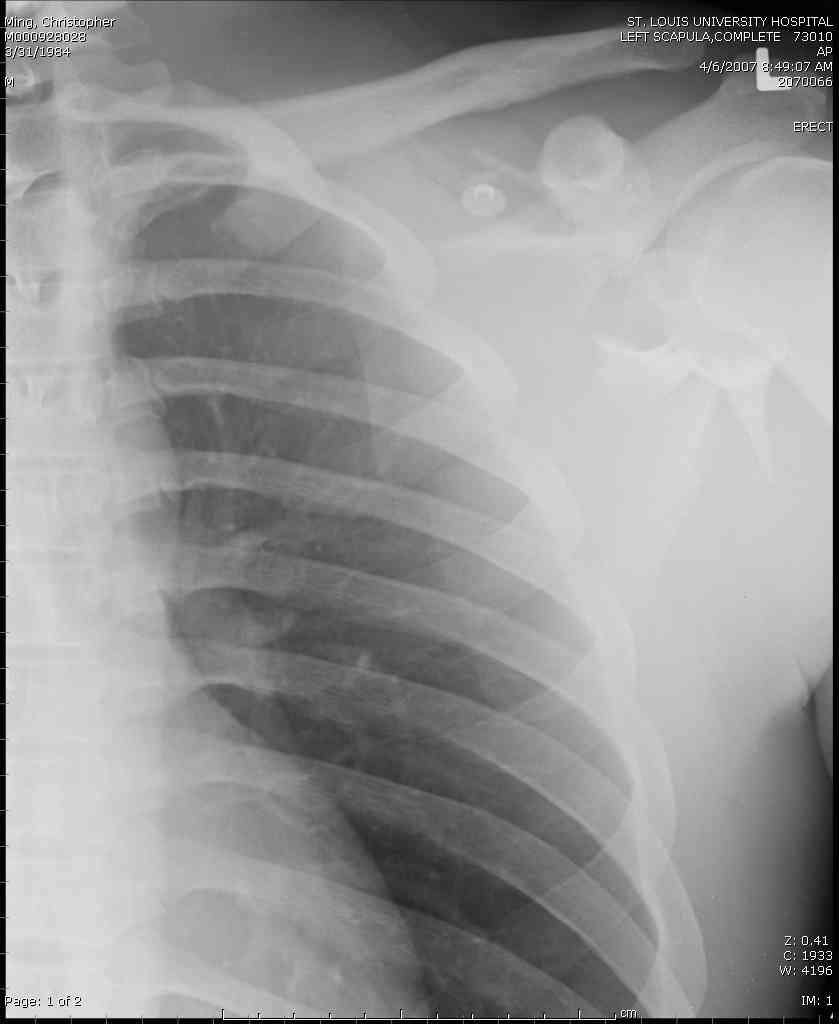

Если у вас имеется доказательство, что перелом лопатки изолированный, тогда нет необходимости операции, потому что стабильные изолированные переломы лопатки срастаются хорошо из-за хорошего кровоснабжения.

Для решения насчет оперативного вмещательства на лопатке сперва надо определиться с обьязательными ренгенологическими исследованиями, не менее трех стандартных проекций: прямая, аксиллярная и в позиции виде “Y”.

К-томографические и Трехмерные(3D)снимки крайне важны для определения внутрисуставных переломов и классификации.

Кроме анатомической классификации, переломы лопатки делятся на стабильные и нестабильные, внутри- и внесуставные и с вовлечением суставной поверхности.

Нестабильные внесуставные переломы лопатки типично сочетаются с переломами ключицы и ребер.

При отсутствии соединения верхнего пояса с телом из-за перелома ключицы и шейки лопатки имеется состояние "floating shoulder", как в аналогии повреждения около коленного сустава "floating knee" при переломах костей выше и ниже коленного сустава.

В таких случаях, когда нет больших смещений на стороне суставной поверхности, и нет необходимости операции на лопатке, тогда ограничиваются фиксацией только ключицы, то есть фиксируется верхняя конечность к туловищу через ключицу...

Также показания к оперативному вмещательству на лопатке появляются, когда смещения суставной поверхности медиально 9 и более мм и при угловом смещении суставной поверхности 40 и более градусов.

В 1993 Goss описал верхне плечевой поддерживающий комплекс (SSSC-superior shoulder suspensory complex), костно-связочное кольцо из акромиона, коракоида, ключицы и гленоида. Повреждения двух или более элементов из перечисленных доказывают наличие флотирования, и рекомендуется операция.